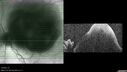

Central Retinal Vein Occlusion with cilioretinal artery occlusion72 views63 year old female who lost vision in the left eye 2 days ago. She was in the emergency room and had a lot of tests done which were all reportedly normal. The right eye is OK.

VA OD: Dcc20/25 NccJ2

VA OS: Dcc20/200-1 PHNI Ncc20/400-1

IOP: TP: OD:11 OS:12